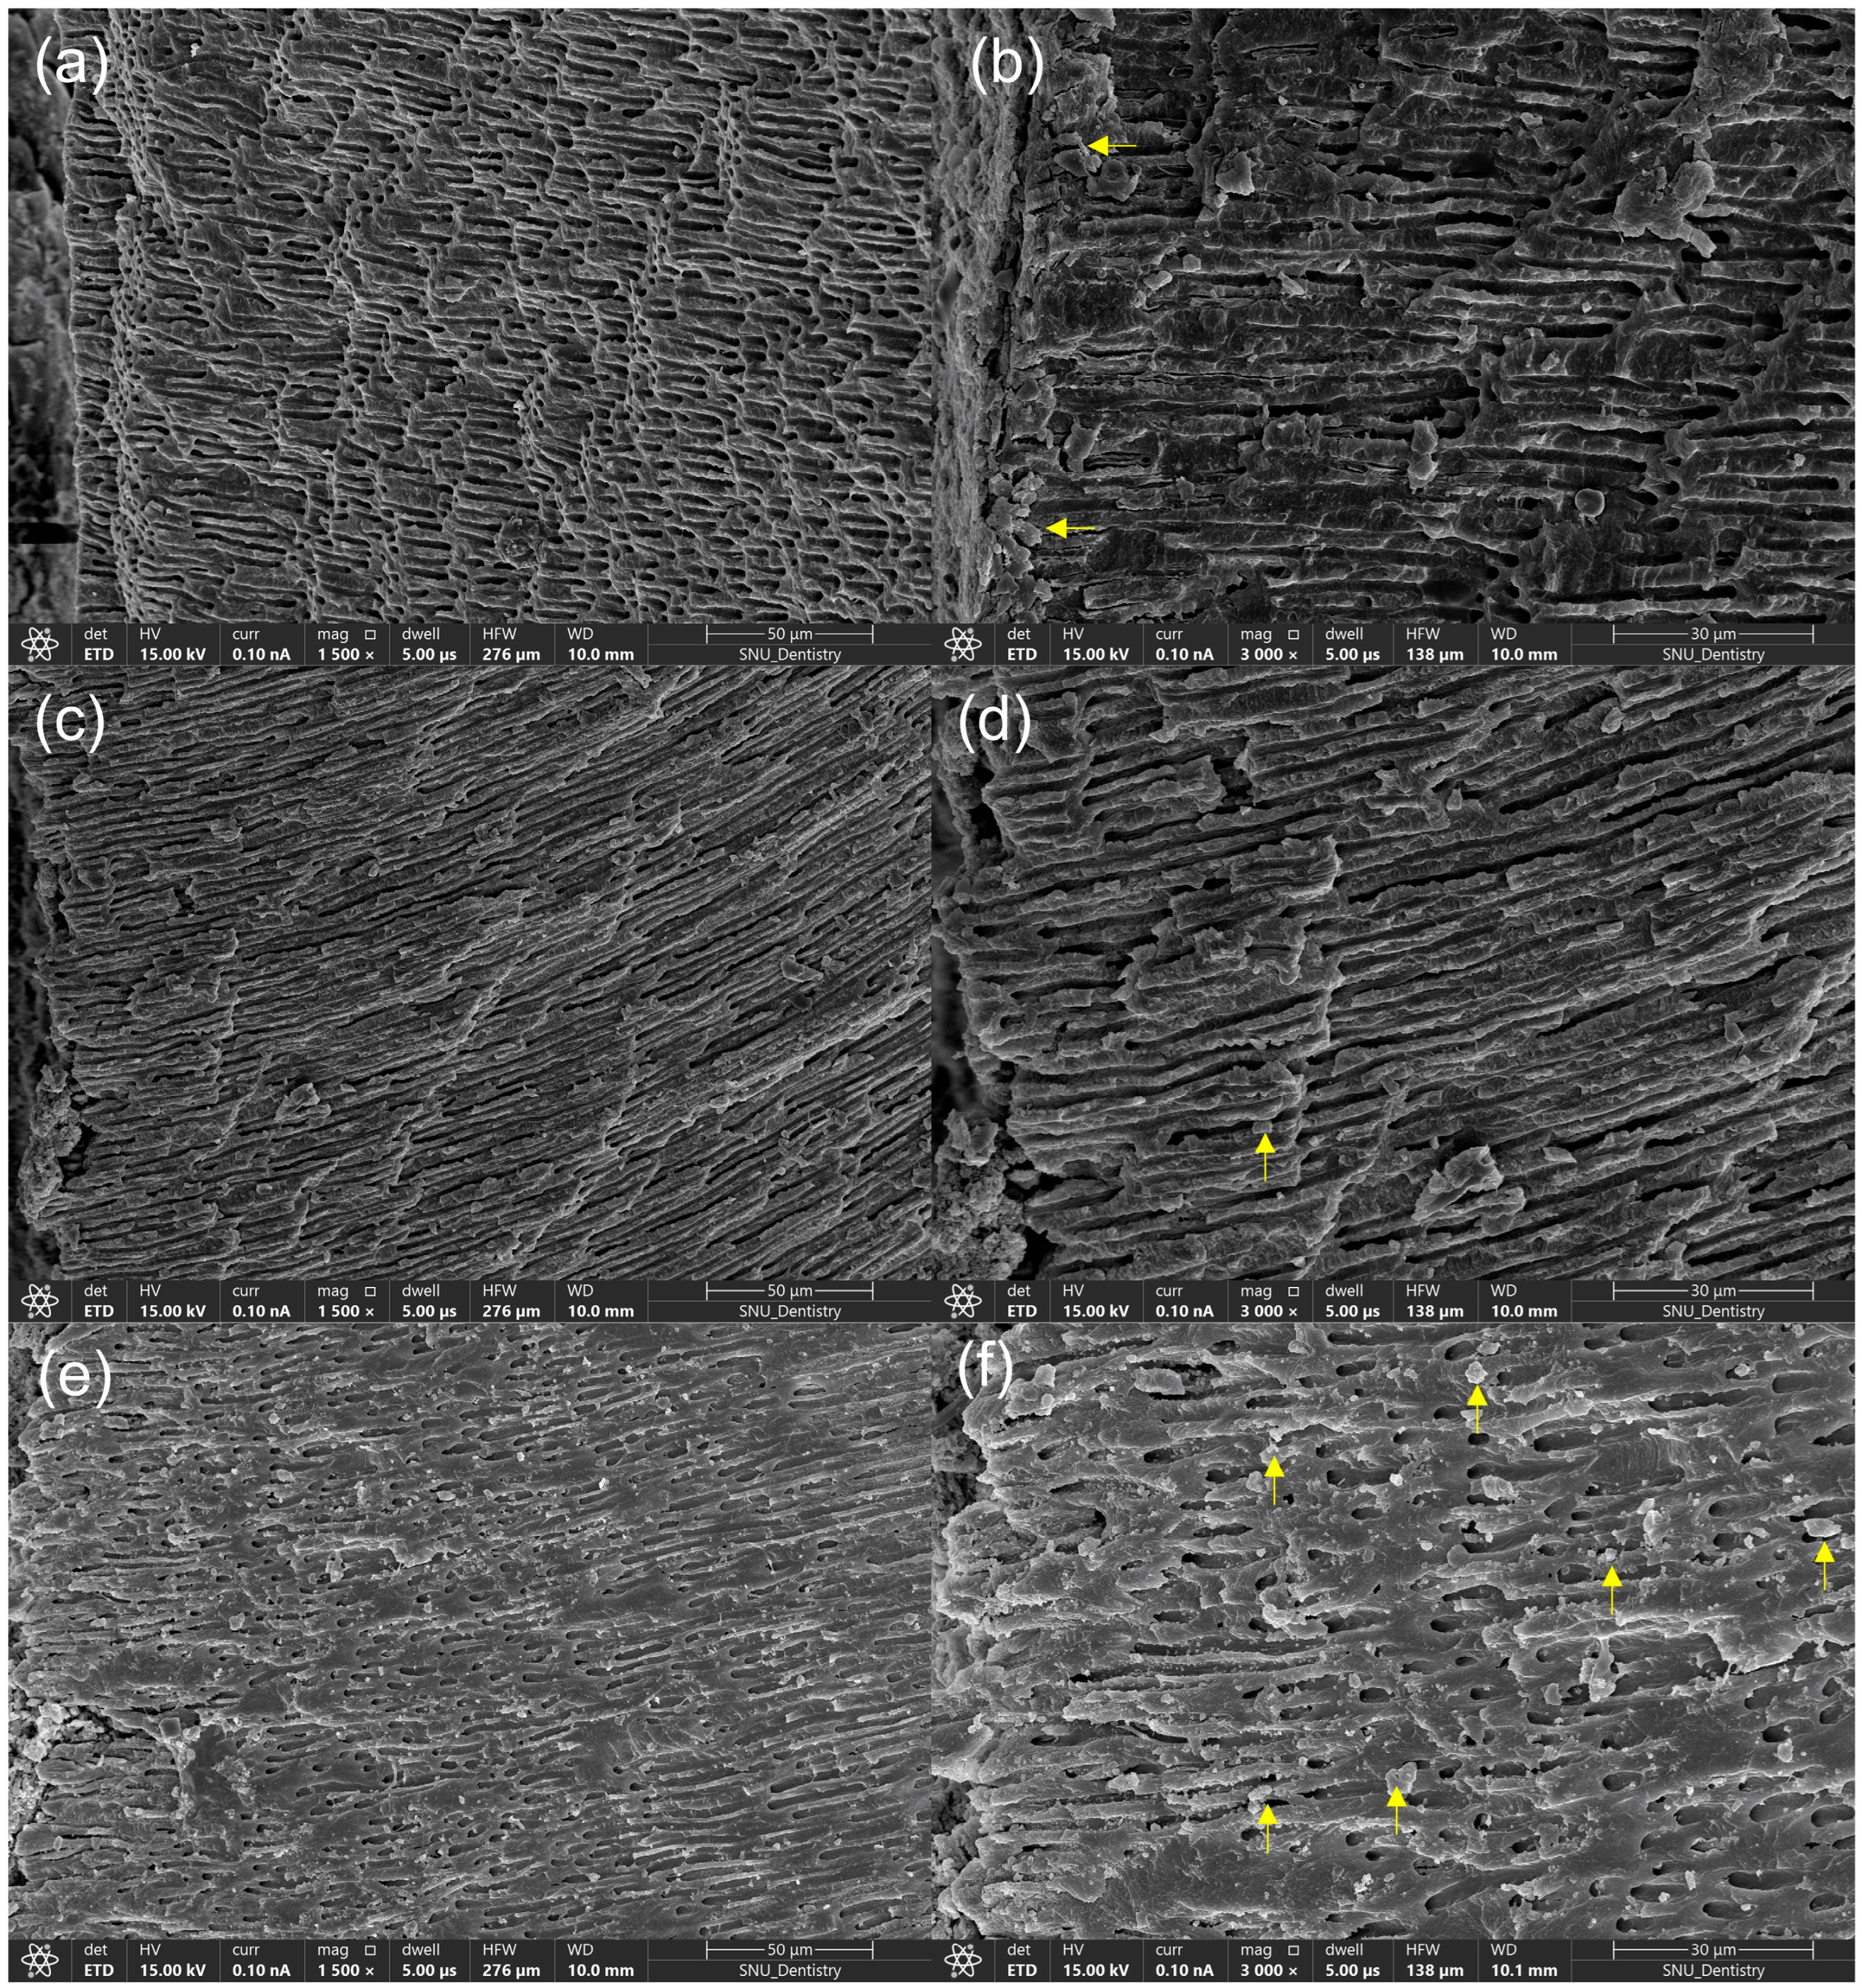

3.5. FE-SEM Examination